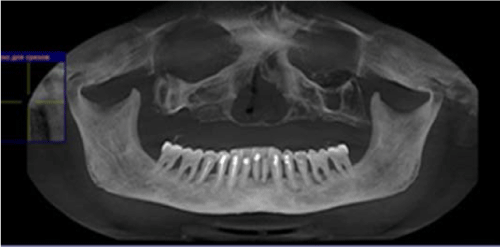

A 46 years old patient, presented to our clinic with a diagnosis of generalized periodontitis of the lower jaw, with edentulous atrophic maxilla. A comprehensive clinical and radiographic evaluation revealed advanced alveolar bone resorption rendering the prognosis of all lower teeth unfavorable. After the preliminary clinicalradiation examination, a treatment plan was defined that included the removal of all the teeth of the mandible and the installation of 8 dental implants in lower jaw, the installation of 1 dental implants in the tuber regions of the upper jawbone on both sides, the installation of 2 dental implants in zygomatic bone from both sides and installation 4 dental implants in the area of 13,14,23,24 distant teeth. 4 months after implant placement prosthetic restoration was fabricated and adjusted. The patient has been followed up for 5 years. So far, no further problem has occurred and the restoration has remained functional (Figures1-8).

Figure 1: Preoperative CT scan.

Figure 8: CT scan after prosthetic rehabilitation